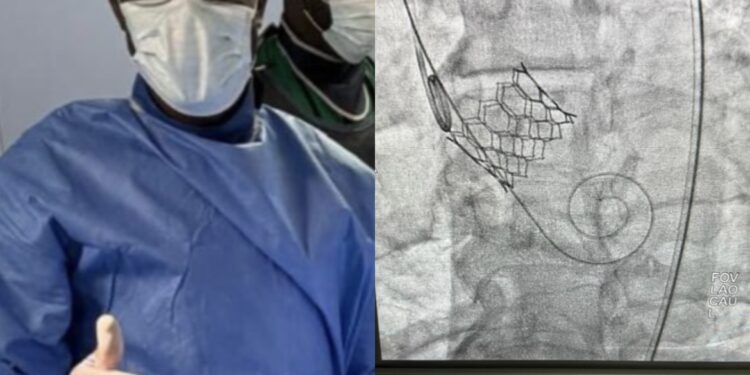

Pour la première fois en Afrique de l’Ouest, en Afrique subsaharienne et en dehors de l’Afrique du Sud, des valves et des prothèses biologiques ont été implantées au niveau de la valve aortique chez les patients cardiaques.

Selon le Pr Mohamed Chérif Mboup, cardiologue et chef du service de cardiologie de l’Hôpital Principal de Dakar, cette implantation a été réalisée de manière percutanée, sans ouvrir le thorax, en passant par les artères fémorales.

«C’est une intervention qui présente plusieurs avantages. D’abord, par rapport à la chirurgie ouverte, il s’agit d’une technique mini-invasive qui ne nécessite ni thoracotomie ni anesthésie générale. Elle est parfaitement adaptée aux sujets âgés et fragiles qui présentent cette pathologie. Les patients, dès le lendemain, sont mobiles et peuvent généralement rentrer chez eux», a expliqué le Pr Mohamed Chérif Mboup.